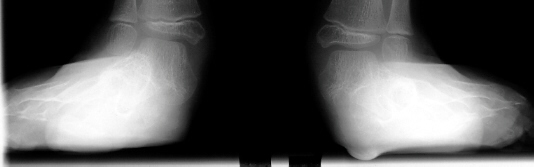

Following

correction of the planovalgus feet, lengthening of the gastrocnemius

is going to be required.

good long term correction of these feet can be expected with only

a lateral column calcaneal lengthening.